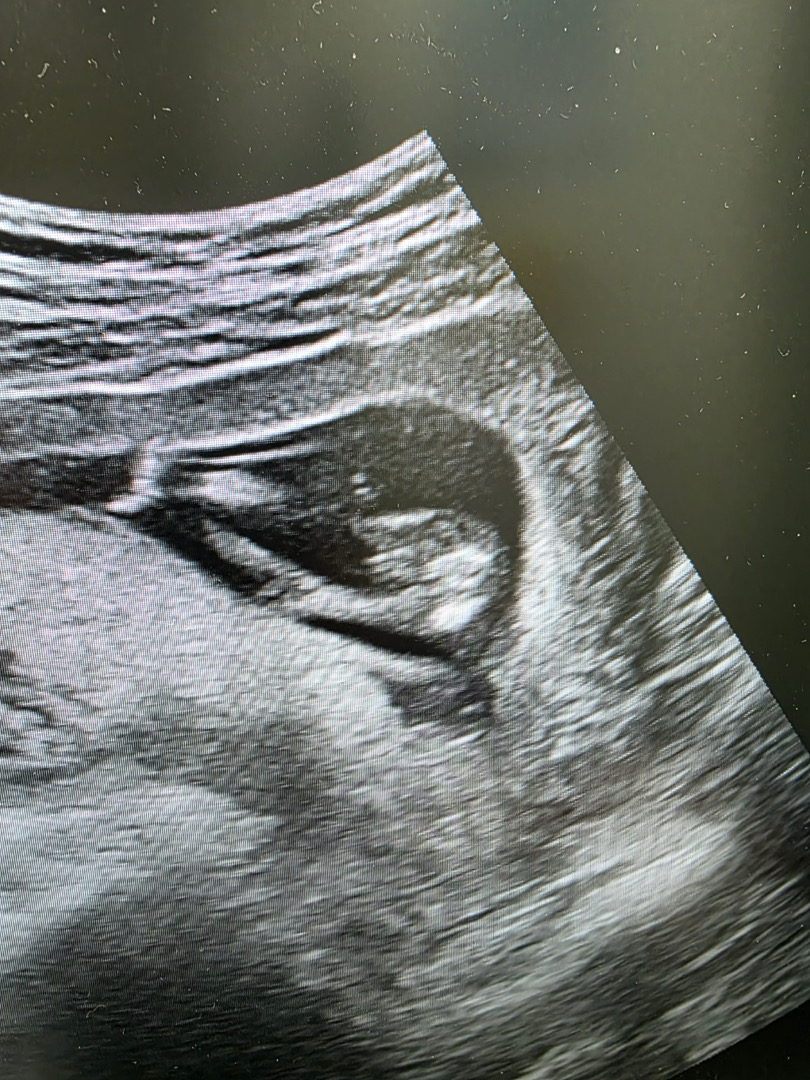

13주 4일차 초음파 성별 봐주세욭

제가 첫째가 딸이라 아들 초음파를 잘몰라서요! 저번주까지는 다리사이가 매끈했는데 오능늠 뭔가보이는거같은데 고추 맞을까요?!

엇..고추같아보이는데 남동생 너무 귀엽겠네요!!